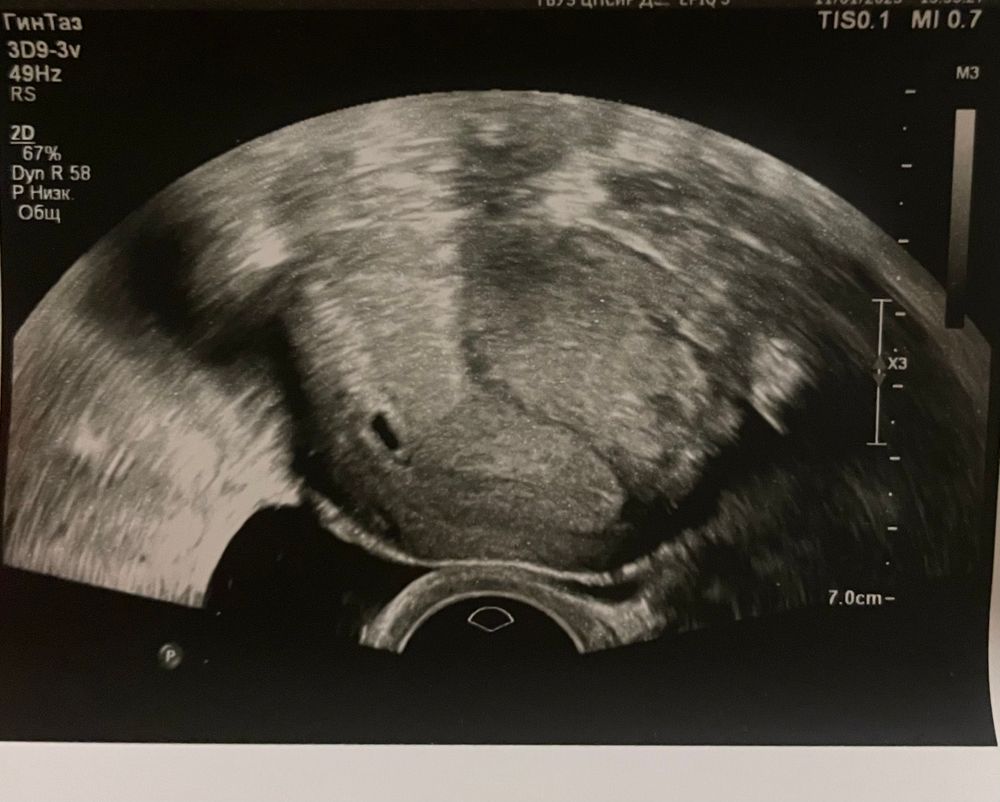

(фото узи прилагаю)

была на узи (тк знаю ,что после хгч 1.500 уже модно увидеть ПЯ)

По фото не определить размер,но думаю все соответствует вашему сроку,так как размер пя зависит от уровня хгч,у вас хгч хороший и по сроку,у меня в одну беременность на 21 дпо хгч 1990 УЗИ на 22 дпо пя 7 мм и никто не говорил,что оно не соответствует сроку,все по сроку было

1) а размеры то какие не понравились врачу? На вид там даже желточный мешок уже есть.